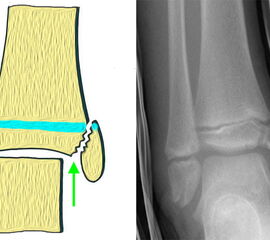

Bei relevanten Axialtraumata kreuzt der Frakturspalt den epiphysären Anteil der Wachstumsfuge (Fugengelenkfraktur, Aitken II und III), mit entsprechenden Risiko das Wachstum zu beeinflussen. Die verschiedenen Klassifikationssysteme der Frakturen im Wachstumsalter sind in Abbildung 2 45 dargestellt.

Fugengelenkfrakturen können die Wachstumsfuge durchkreuzen (Abbildung 16a), ohne oder nur mit minimaler Beteiligung der Fuge sehr weit medial liegen (Abbildung 16b) oder durch die Fuge auslaufen (Abbildung 16c). Relevant für die Wachstumsprognose ist weniger die Form der Fraktur, sondern das Alter des Patienten zum Zeitpunkt des Traumas sowie das Ausmaß der Schädigung der Wachstumsfuge, wobei eine Korrelation mit dem Ausmaß der Dislokation besteht.